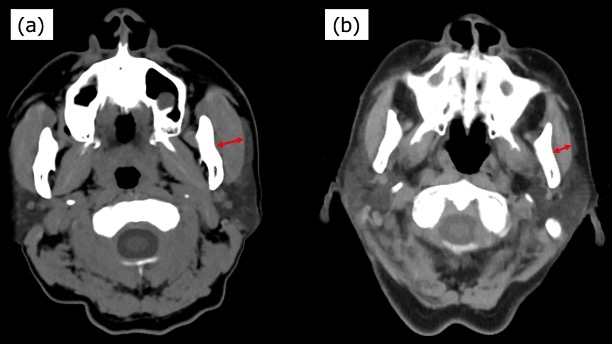

Methods: This retrospective cohort study included 275 consecutive adult patients (median age, 72 years) who underwent elective cardiac surgery between July 2021 and December 2023. Preoperative oral frailty was assessed using the Oral Frailty 5-item Checklist (OF-5; subjective) and masseter muscle thickness on CT (objective; muscle loss defined as ≤25th percentile: males ≤10 mm, females ≤8 mm). Independent predictors of aspiration pneumonia were identified by multivariable logistic regression. Model performance was evaluated using ROC analysis and internally validated using bootstrap resampling to correct for optimism.